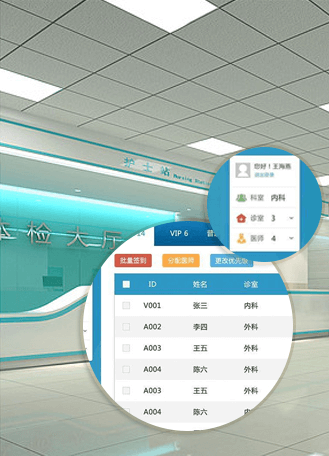

WHOLE PROCESS INTELLIGENT SOLUTION

全流程智慧化解決方案

行業解決方案

醫院體檢中心、專業體檢中心

疾控中心、職防院等

系統功能全面覆蓋10大分類100+版塊全面覆蓋體檢中心業務(基本信息管理、檢前、檢中、檢后、質控、財務、數據互聯、數據上報、數據分析)

支持多檢合一職業體檢、健康體檢、從業體檢、學生體檢、慢病體檢、老年人體檢、8023體檢、婦幼體檢、醫保體檢